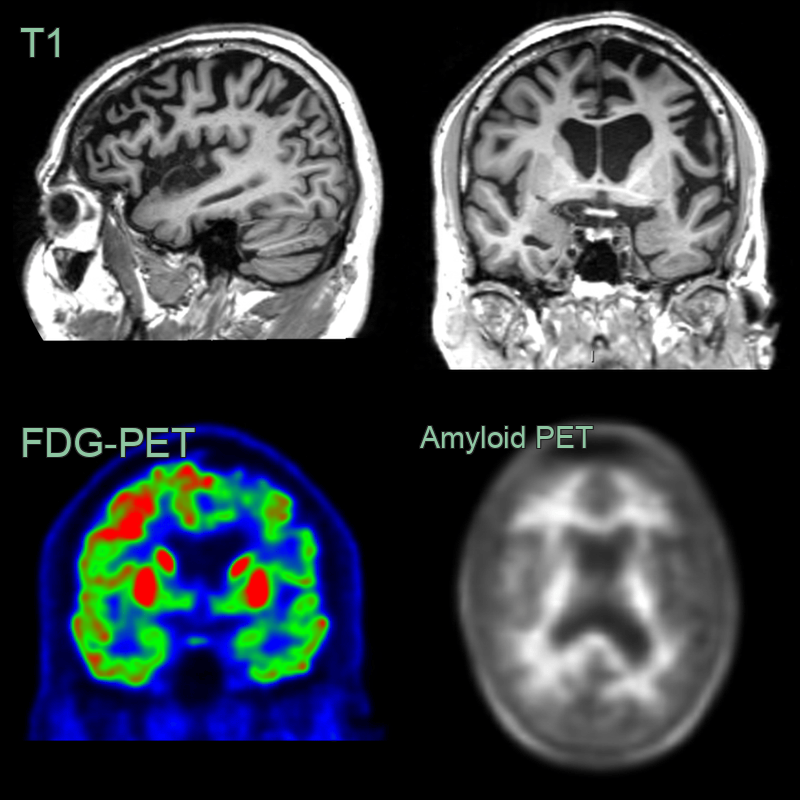

- 60-year-old patient presented with behavioural change and speech changes.

- MRI showed left frontal and temporal atrophy; the superior frontal gyrus was knife-blade thin.

- FDG-PET showed marked hypometabolism in the frontal and temporal lobes.

- Amyloid PET was negative with preserved grey-white matter differentiation.